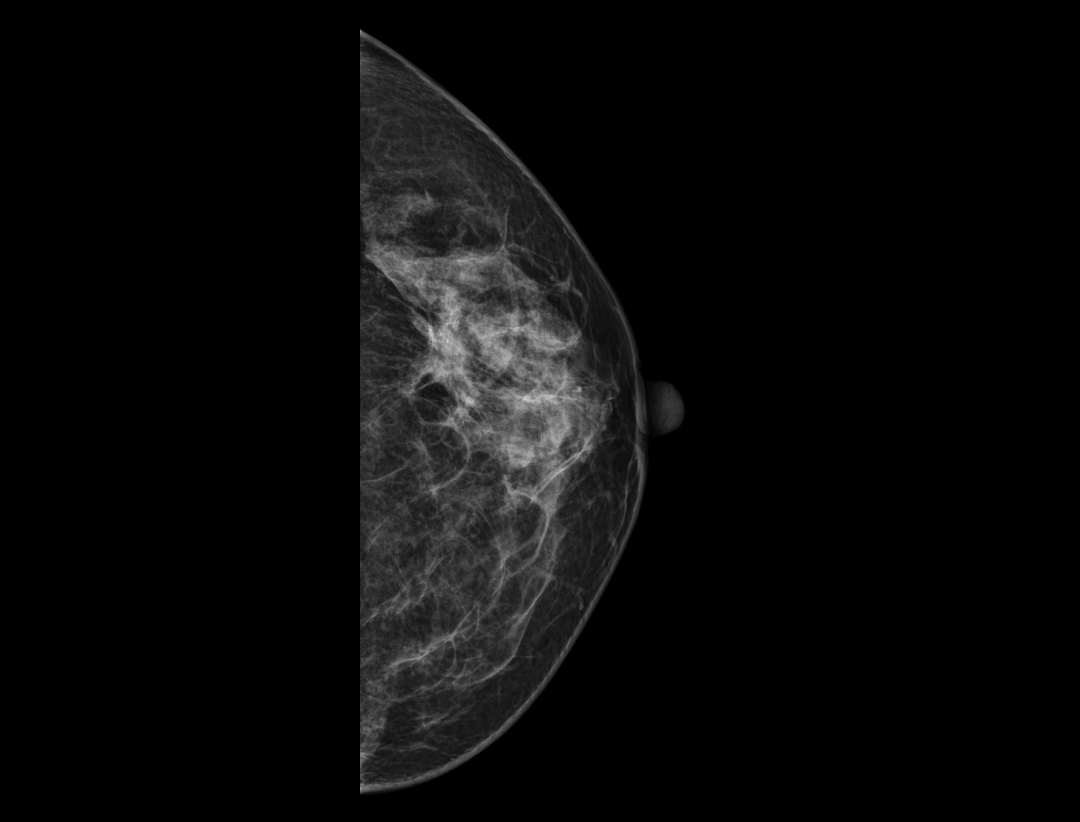

自定义层厚融合

更精细观察肿块及钙化簇的空间分布。